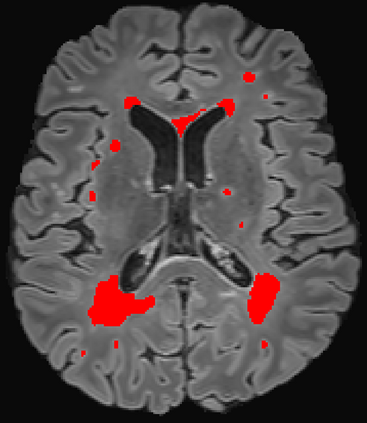

Assessment of lesions and their longitudinal progression from brain magnetic resonance (MR) images plays a crucial role in diagnosing and monitoring multiple sclerosis (MS). Machine learning models have demonstrated a great potential for automated MS lesion segmentation. Training such models typically requires large-scale high-quality datasets that are consistently annotated. However, MS imaging datasets are often small, segregated across multiple sites, with different formats (cross-sectional or longitudinal), and diverse annotation styles. This poses a significant challenge to train a unified MS lesion segmentation model. To tackle this challenge, we present SegHeD, a novel multi-dataset multi-task segmentation model that can incorporate heterogeneous data as input and perform all-lesion, new-lesion, as well as vanishing-lesion segmentation. Furthermore, we account for domain knowledge about MS lesions, incorporating longitudinal, spatial, and volumetric constraints into the segmentation model. SegHeD is assessed on five MS datasets and achieves a high performance in all, new, and vanishing-lesion segmentation, outperforming several state-of-the-art methods in this field.